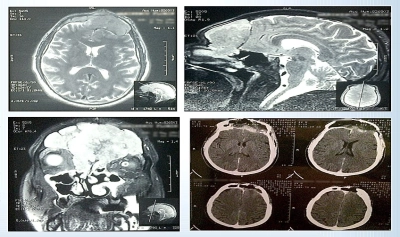

Valentin Munteanu, medic primar Neurochirurgie în cadrul Spitalului Clinic Sanador, își face meseria deseori la cote imposibile. Pentru asta e nevoie de mâini de robot, curaj, fler și multă știință de carte. Imagistica alăturată ne arată un bolnav de 60 de ani aflat la limita dintre viață și moarte.

Observăm un carcinom neuroendocrin crescut masiv într-o zonă ultra-sensibilă, plecat de undeva din spatele nasului, inserat în cutia craniană comprimând serios creierul. Tumora, infiltrativă, cu origini etmoidale, invadase inclusiv sinusul frontal stâng și duramater - primul strat al meningelui, membrana care acoperă parenchimul cerebral. Ea fusese descoperită la un control ORL cu pacientul reclamând dureri de cap, pierderea mirosului, amețeli.

Proliferarea malignă a distrus etajul anterior al bazei craniului lăsând practic o comunicare deschisă între creier și nas! A fost eliminată printr-un abord fronto-sinusal, cu multă migală, din cauza caracterului infiltrativ care a dus și la formarea de puroi în sinus. Apoi a trebuit refacut totul prin plastie osteo-fibroasă cu țesut recoltat de la bolnav. Șase ore de migală și precizie utilizând CUSA (Cavitron Ultrasonic Surgical Aspirator) și, evident, faimosul microscop Zeiss Kinevo.